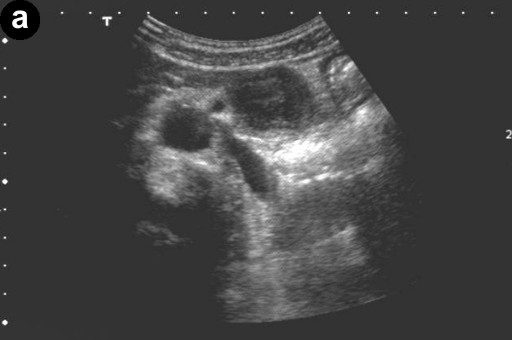

A 66-year-old Japanese woman was admitted to our hospital with a pancreatic tumor indicated in medical examinations. There was no remarkable past history of disease. No inherited factors or marked diseases in her family were noted. On admission, she had no complaints, and physical examinations and laboratory data revealed no noticeable abnormalities. Serum levels of CA 19-9 and s-pancreas-1 (pancreatic associated) antigen were within the normal range. Magnetic resonance imaging (MRI) revealed a mass, 3 cm in diameter, in the body of the pancreas, showing hypointensity on T1-weighted images, marked enhancement after gadolinium diethylenetriaminepenta acetic acid (Gd-DTPA) administration, and mixed hypo- and hyperintense patterns on T2-weighted images (Figure 1abc). Magnetic resonance cholangiopancreatography (MRCP) and endoscopic retrograde cholangiopancreatography (ERCP) showed no abnormal findings. The results of bacterial cultures of the pancreas juice were negative. Computed tomography (CT) revealed a 3 cm solid and cystic tumor within the body of the pancreas, with high resorption CT levels of the cystic components (Figure 1d). Contrast-enhanced CT showed partial enhancement of the solid components, and the main pancreatic duct was not involved in the tumor. Ultrasonography (US) and endoscopic ultrasonography (EUS) revealed a 3 cm solid and cystic tumor with low echoic margins in the body of the pancreas (Figure 2a). Contrast-enhanced US with Levovist® (Bayer Schering, Berlin, Germany) showed partial enhancement of the solid components (Figure 2b). Angiography showed no abnormal findings. From these imaging findings, mucinous cystic neoplasms or acinar cell tumors were considered.

Figure 2. a. US reveals a solid and cystic tumor with low echoic margin in the body of the pancreas. b. Contrast-enhanced US with Levovist® (Bayer Schering, Berlin, Germany) shows partial enhancement at the solid component. |

The solid and cystic pattern observed on CT was also seen with US, in which hypoechoic and/or cystic findings were noted in a high percentage of cases. However, the details of the solid components were revealed more clearly by US as compared to CT or MRI. Moreover, in the present case, contrast-enhanced US with Levovist® (Bayer Schering, Berlin, Germany) showed partial enhancement at the solid component.